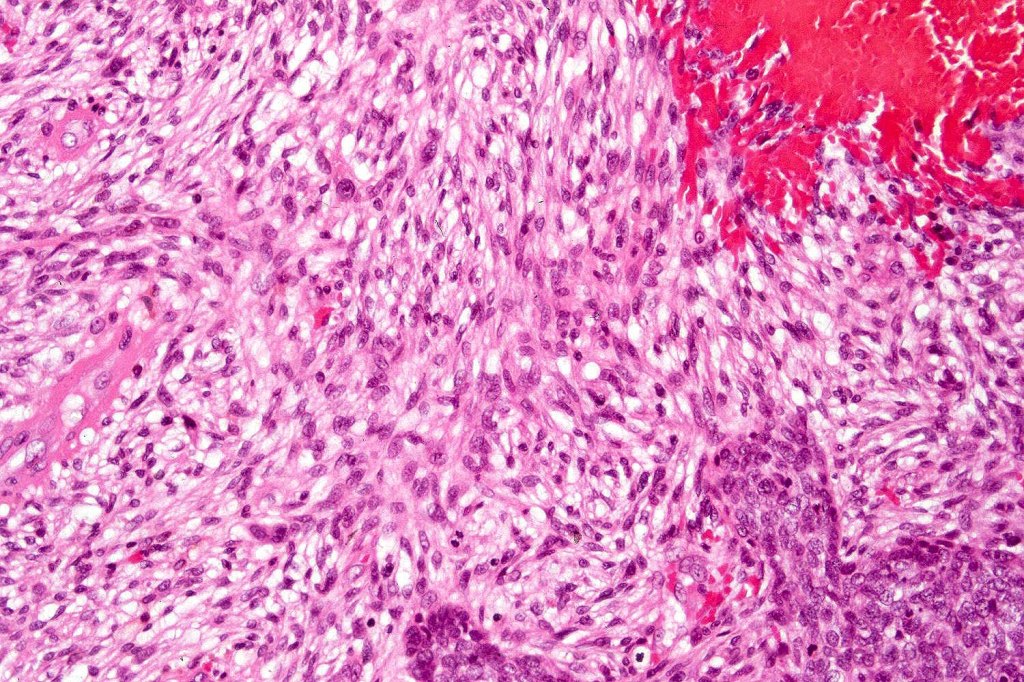

Carcinosarcoma

Cutaneous carcinosarcoma (metaplastic carcinoma, carcinoma with heterologous differentiation)

Histological features

•Osteoid

•Chondroid

•Smooth muscle

•MFH-like features with osteoclasts

•Neural differentiation